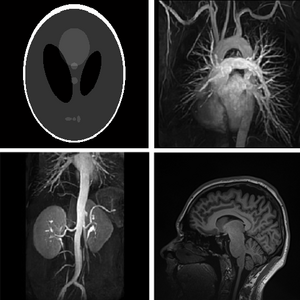

Deep networks for solving challenging image recovery problems

deepmri2

Supervised and Unsupervised Deep Methods for MRI Reconstruction:

1- Deep Plug-and-Play Prior for Parallel MRI Reconstruction (Link)

2- ODE-based Deep Network for MRI Reconstruction (Link)

3- Non-Learning based Deep Parallel MRI Reconstruction (NLDpMRI) (Link)